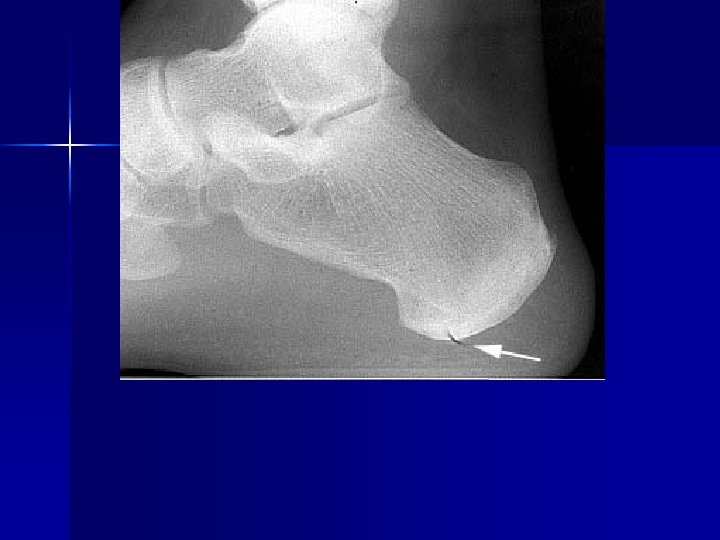

PATHOLOGY NOT ARTIFACT

Name & cause of this?

Evaluating Images What do you think?

n n n Does this show good detail? Is all of the anatomy present? How is the density / contrast?